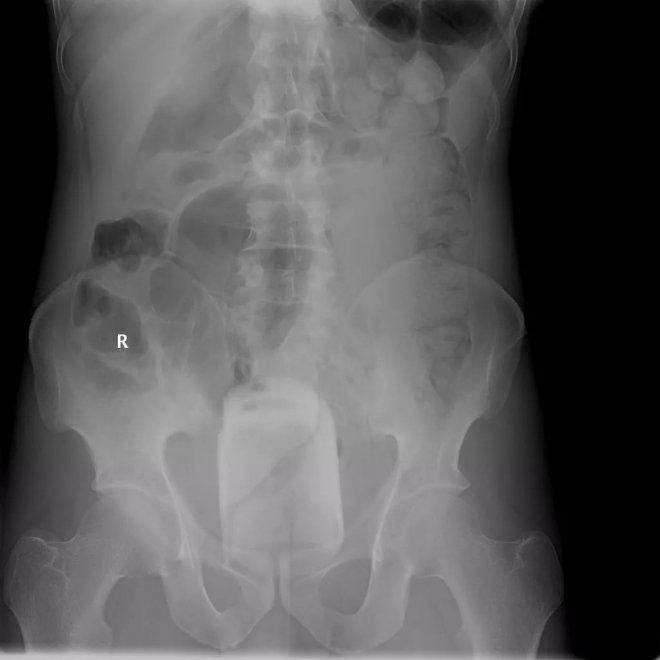

橙子

下腹部中央有一個圓形的異物,原來是患者自己塞進去的橙子。水果雖然是好東西,但不是這樣用法